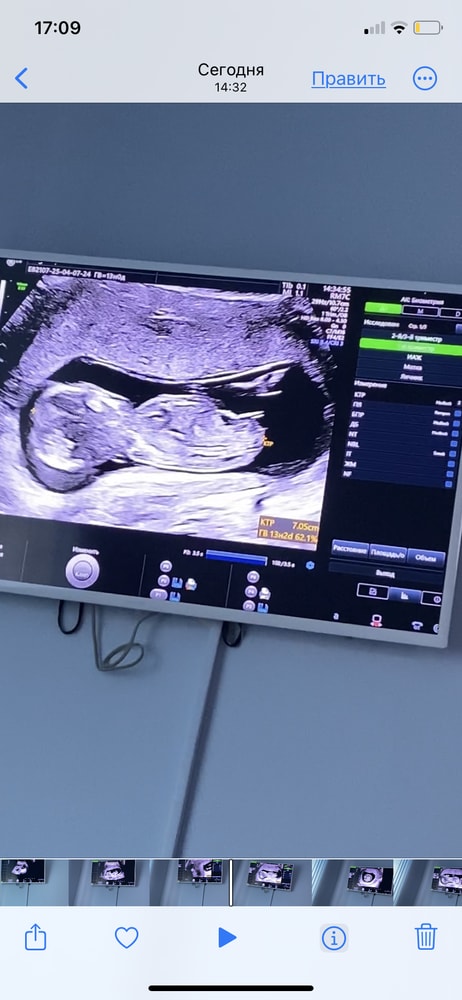

Мне на 12 неделе хороший специалист определил дочь. В 15 уже точно подтвердили. Если спец хороший и аппарат узи,то вполне возможно, что не ошибка

Мне тоже кажется,что девочка. Но точно можно узнать чуточку позже)

с 14 недель только можно определить

Muminlaw, все зависит от аппарата УЗИ и врача. Мне в 11недель и 3 дня сказали что девочка, на последующих УЗИ подтверждали

Мальчика вижу, но я не уверена)

Девочка👍